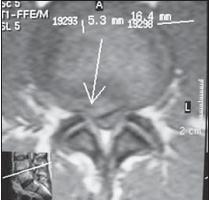

МРТ № 15

МРТ № 16

На МРТ № 15 наблюдается двухсторонняя экстрафораминальная грыжа межпозвонкового диска (расположенная за межпозвонковыми отверстиями)

На МРТ № 16 наблюдается медиолатеральная протрузия и вентральная грыжа межпозвонкового диска